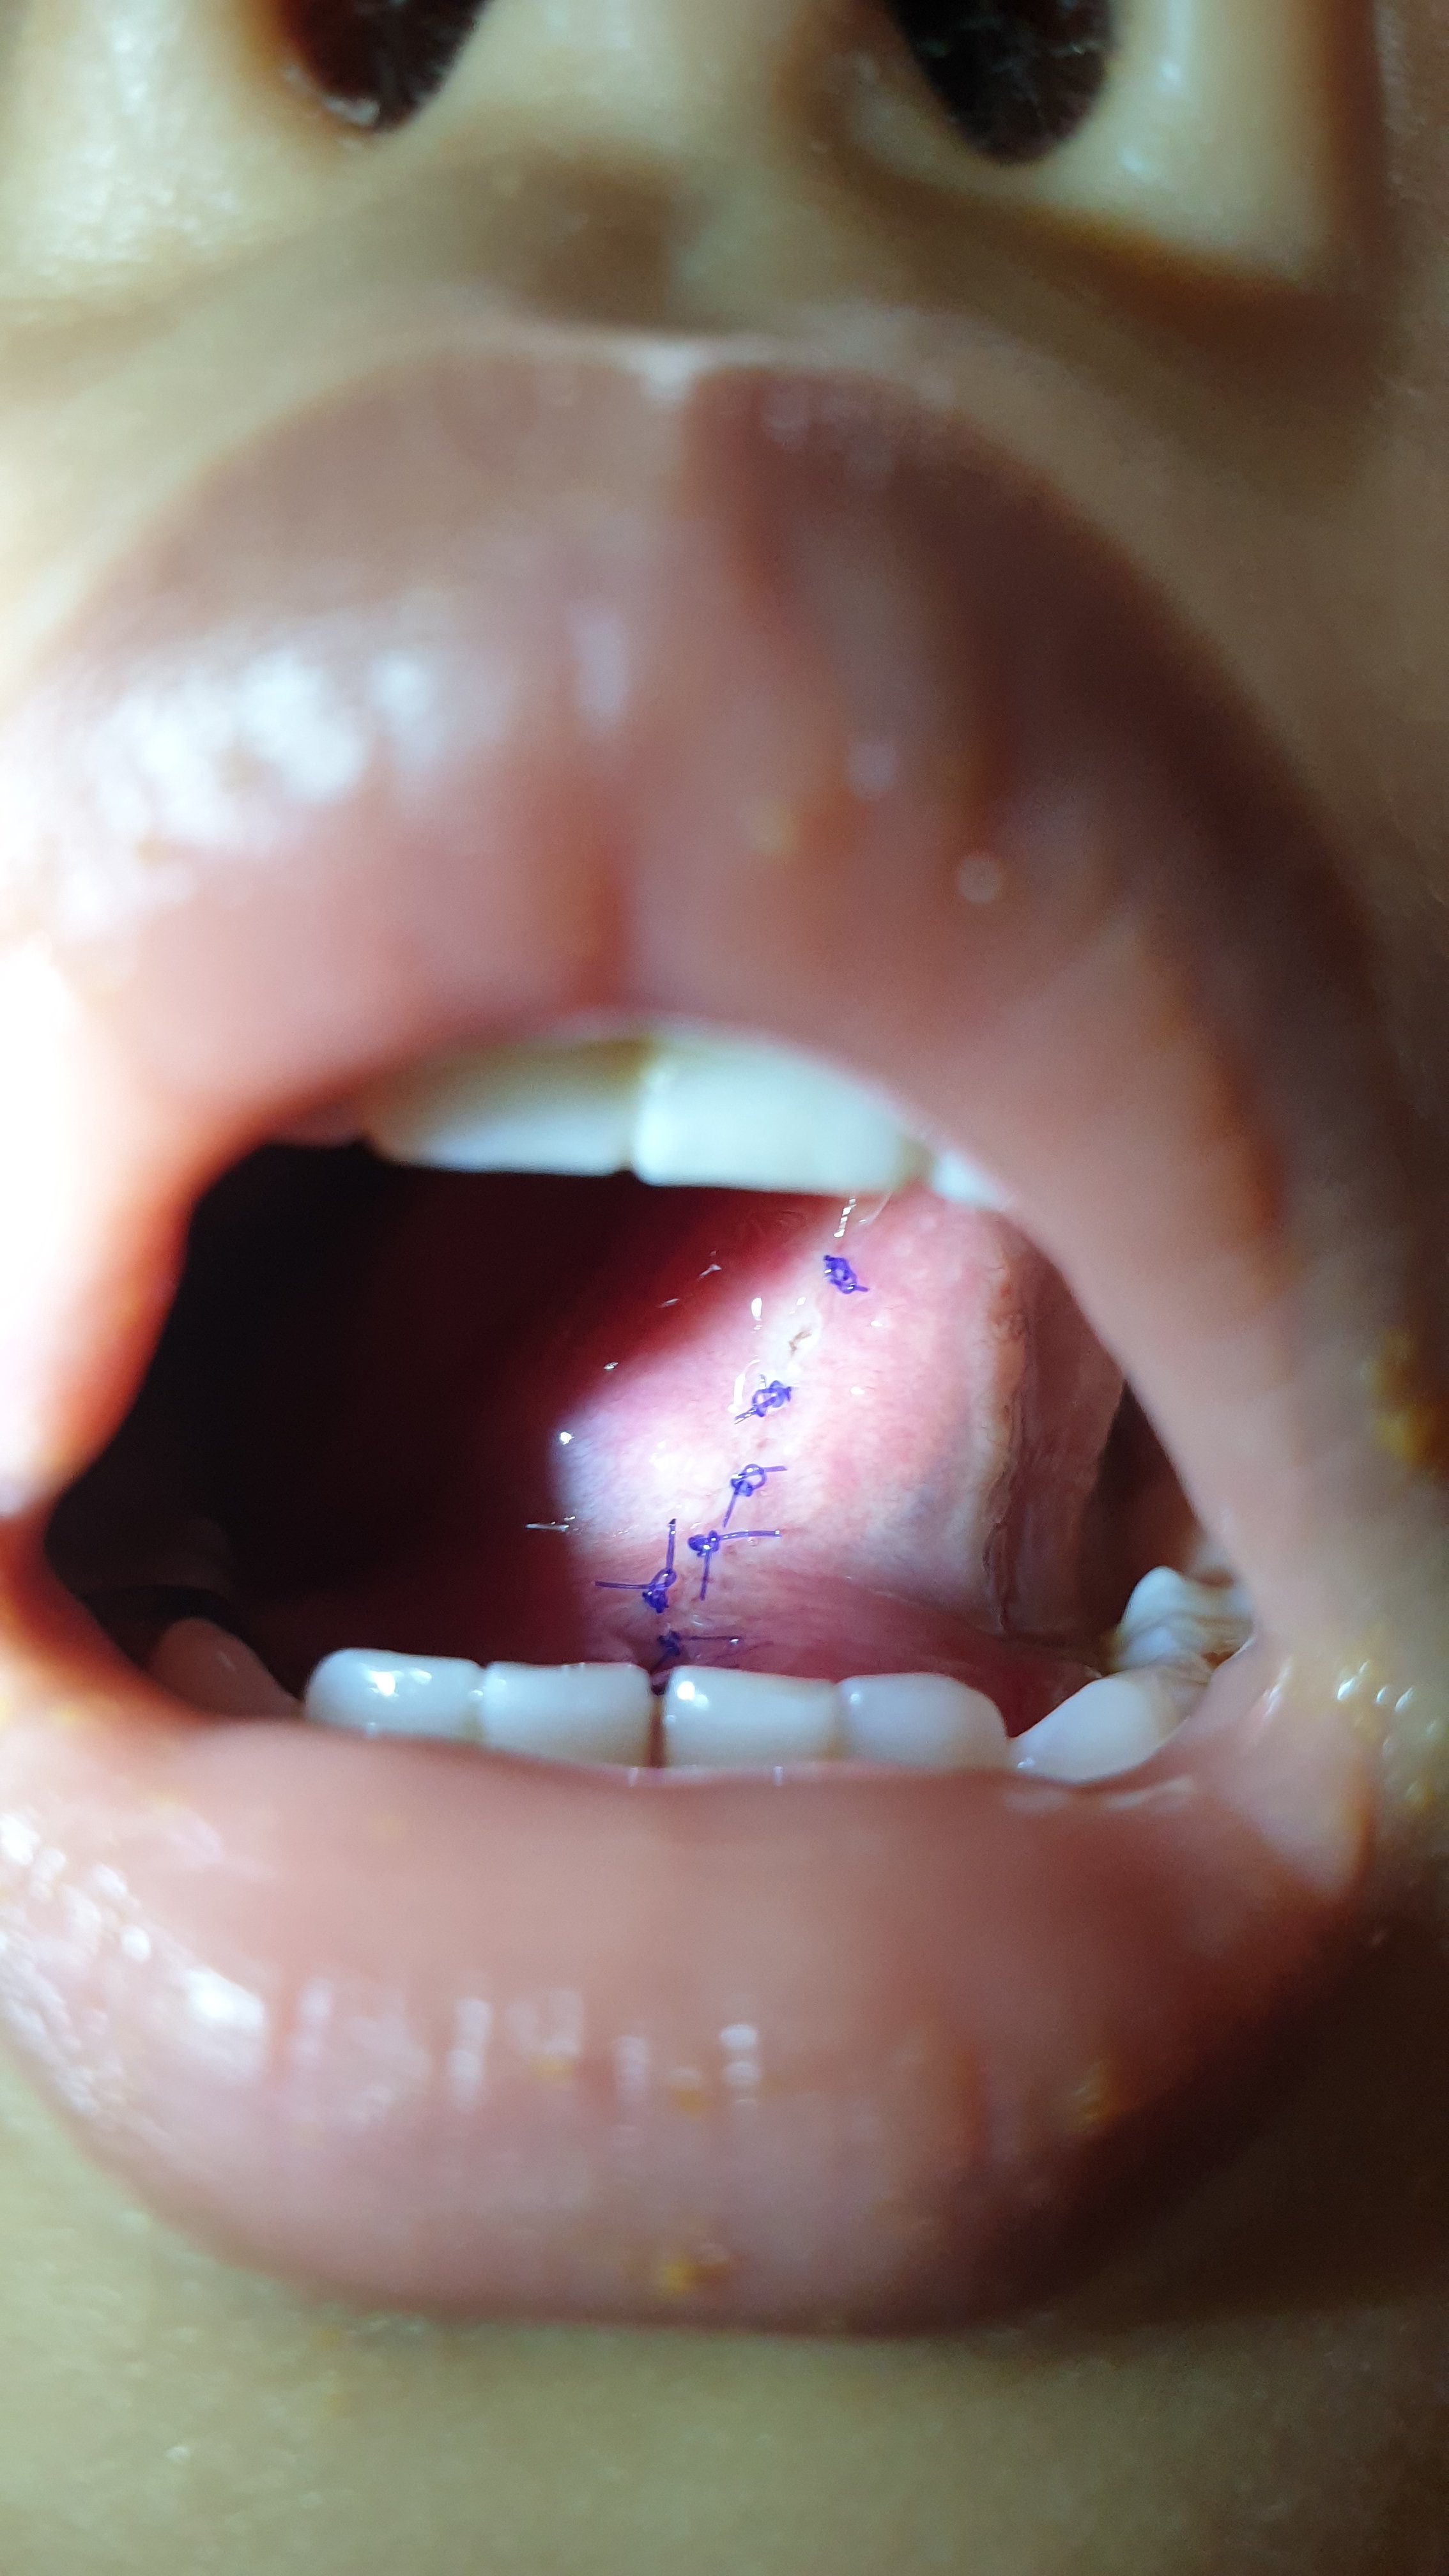

回家後拍的,剪好開。

舌繫帶太緊,舌頭都捲不請來。

剪掉後,舌頭靈活了,平常話就很多,之後可能更多了。